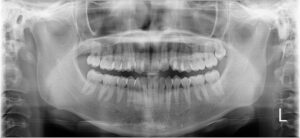

②レントゲン撮影

口全体が映るパノラマレントゲンを撮影します。

レントゲン写真も矯正前→現在で並べてみます。

ぎゅうぎゅうに詰まっていたのが少し緩和されています。

歯根の吸収もないようで一安心です。